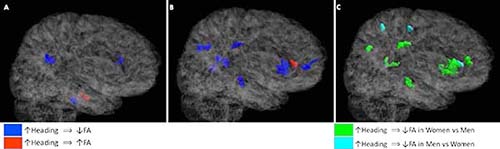

Researchers compared white matter fractional anisotropy (FA) values among the male and female soccer players. The analysis revealed that while both men and women experienced lower FA values related to more repetitive heading, women exhibited lower FA levels across a much larger volume of brain tissue.

Among men, three regions were identified in which a greater number of heading events was significantly associated with lower FA including the genu and splenium of the corpus callosum and the pons. In men, there was only one location, the left temporal white matter, in which a greater exposure to heading was associated with significantly higher FA.

In women, eight regions were identified in which greater heading exposure showed a significant association with lower FA including the genu of the corpus callosum; left occipital, right parietal and right orbitofrontal white matter; left superior longitudinal fasciculus; right cingulum; and right cerebral peduncle.

Overall, an association between greater heading exposure and FA was detected across 2,121 mm3 of white matter in women, compared with 408 mm3 in men.